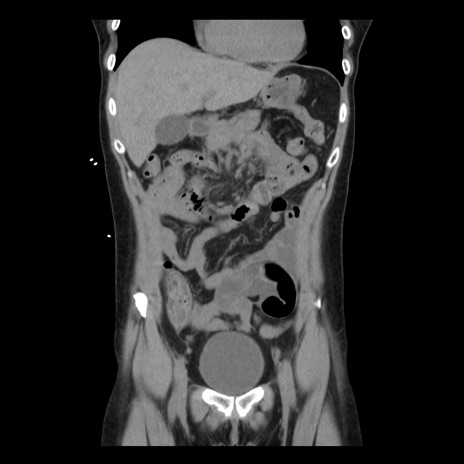

横断像